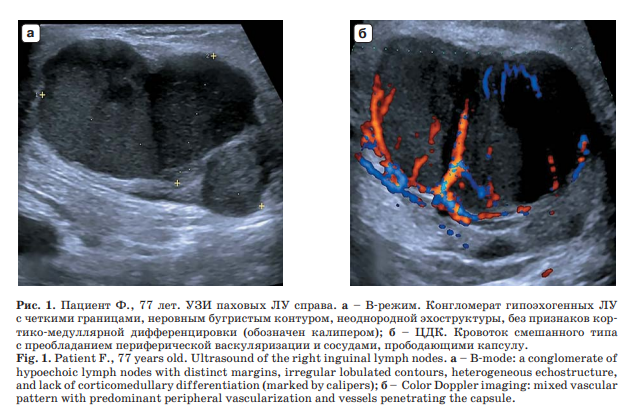

Так, в журнале перечня ВАК РФ «Ультразвуковая и функциональная диагностика» врачом отделения УЗД Панковой Е.А. и зав. отделением УЗД ВОНКОЦ Кругловым И.С. представлены два клинических наблюдения пациентов с меланомой кожи и метастатическим поражением регионарых ЛУ.

Результаты ультразвукового исследования сопоставлены с данным рентгенологических (компьютерная томография с контрастным усилением) и радиологических методов (однофотонная эмиссионная компьютерная томография) и верифицированы данными гистологического исследования операционного материала.

Было установлено, что ультразвуковое исследование позволяет по набору соответствующих признаков заподозрить наличие вторичных изменений в ЛУ при меланоме, что может быть использовано на первой линии диагностики для определения дальнейшего плана обследования и лечения пациентов.